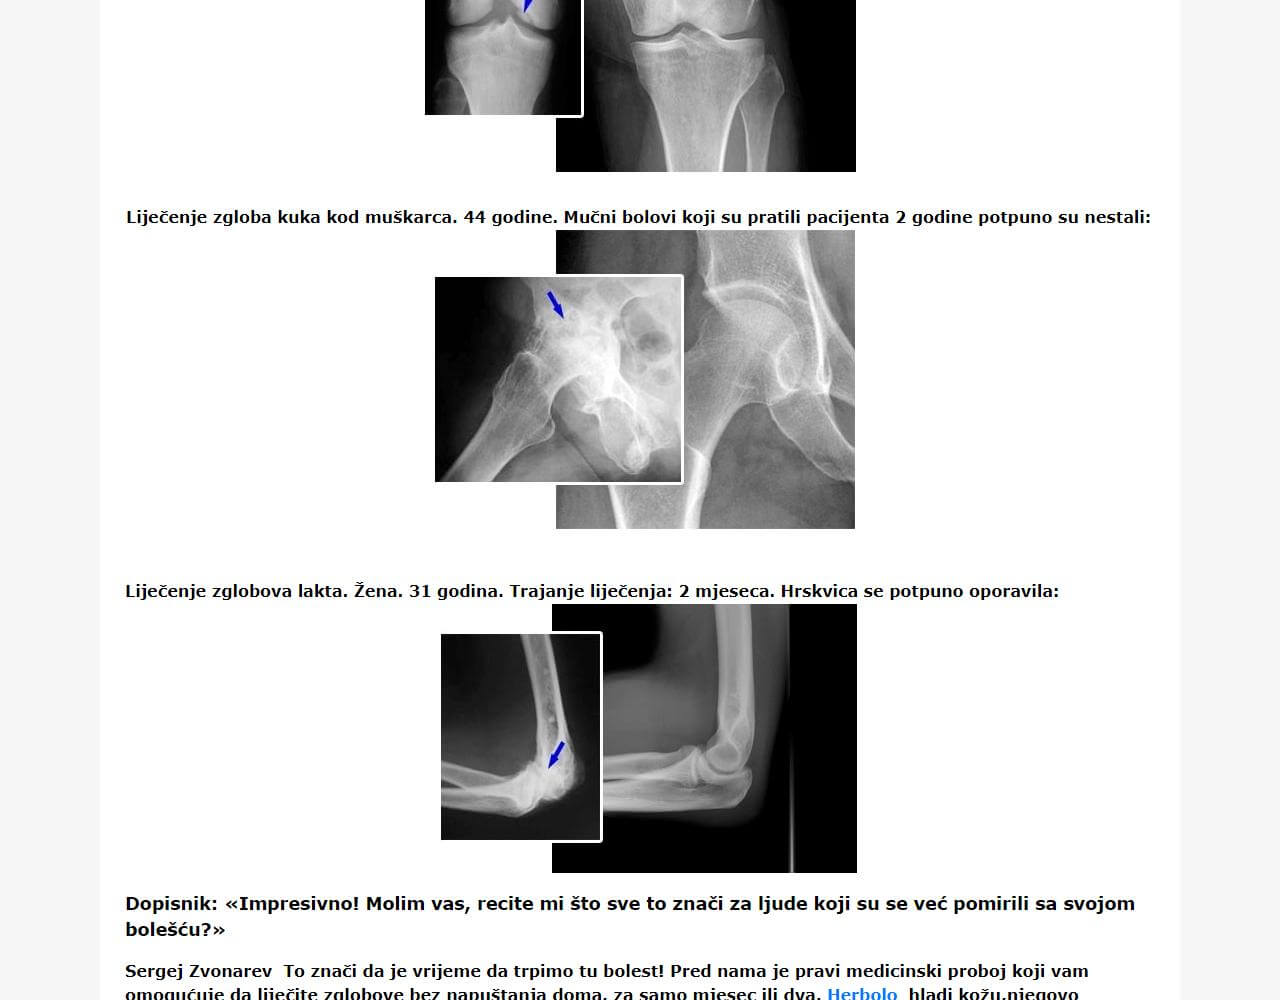

Ne vjerujete u efikasnost predloženog lijeka, misleći da su riječi o djelotvornosti Herbolo prevara? Odbacite skepticizam, jer je njegova terapijska aktivnost klinički dokazana uz učešće ljudi koji boluju od bolesti mišićno-koštanog sistema. Redovna upotreba ovog lijeka oslobodila je 95% ispitanika od bolesti. Jednako je vrijedno da provedena terapija nije negativno utjecala na zdravlje ispitanika.